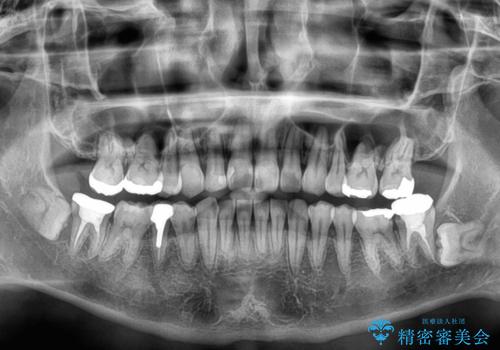

【モニター】八重歯と正中のずれた歯列 片顎抜歯のワイヤー矯正

補助装置を併用することで効率的に八重歯や正中位置の改善を達成することができました。

口元の突出感は感じていなかったことと、奥歯の咬み合わせを考慮し、上顎のみ左右の第一小臼歯を抜歯してワイヤー装置にて矯正治療を行うこととしました。